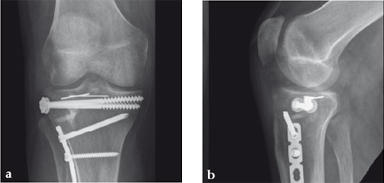

Case 2: A 38-year-old man sustained a lateral tibia plateau fracture (Müller AO Classification 41-B.3/Schatzker type II).

(Case provided by Michiel Verhofstad, Tilburg, The Netherlands)

After opening the lateral wedge, the osteochondral fragment was reduced and maintained with two K-wires. A gap beneath this fragment was left. Subsequently, a 3.2 mm hole was drilled in the lateral wedge using an inside-out technique. Then the lateral fragment was reduced. A 3-hole buttress plate, followed by two subchondral compression screws were used for final fracture fixation. Finally, Norian drillable was injected in the gap through the predrilled hole. Weight bearing was started after 6 weeks. At 6 months the fracture had healed anatomically and the patient was complaint-free.